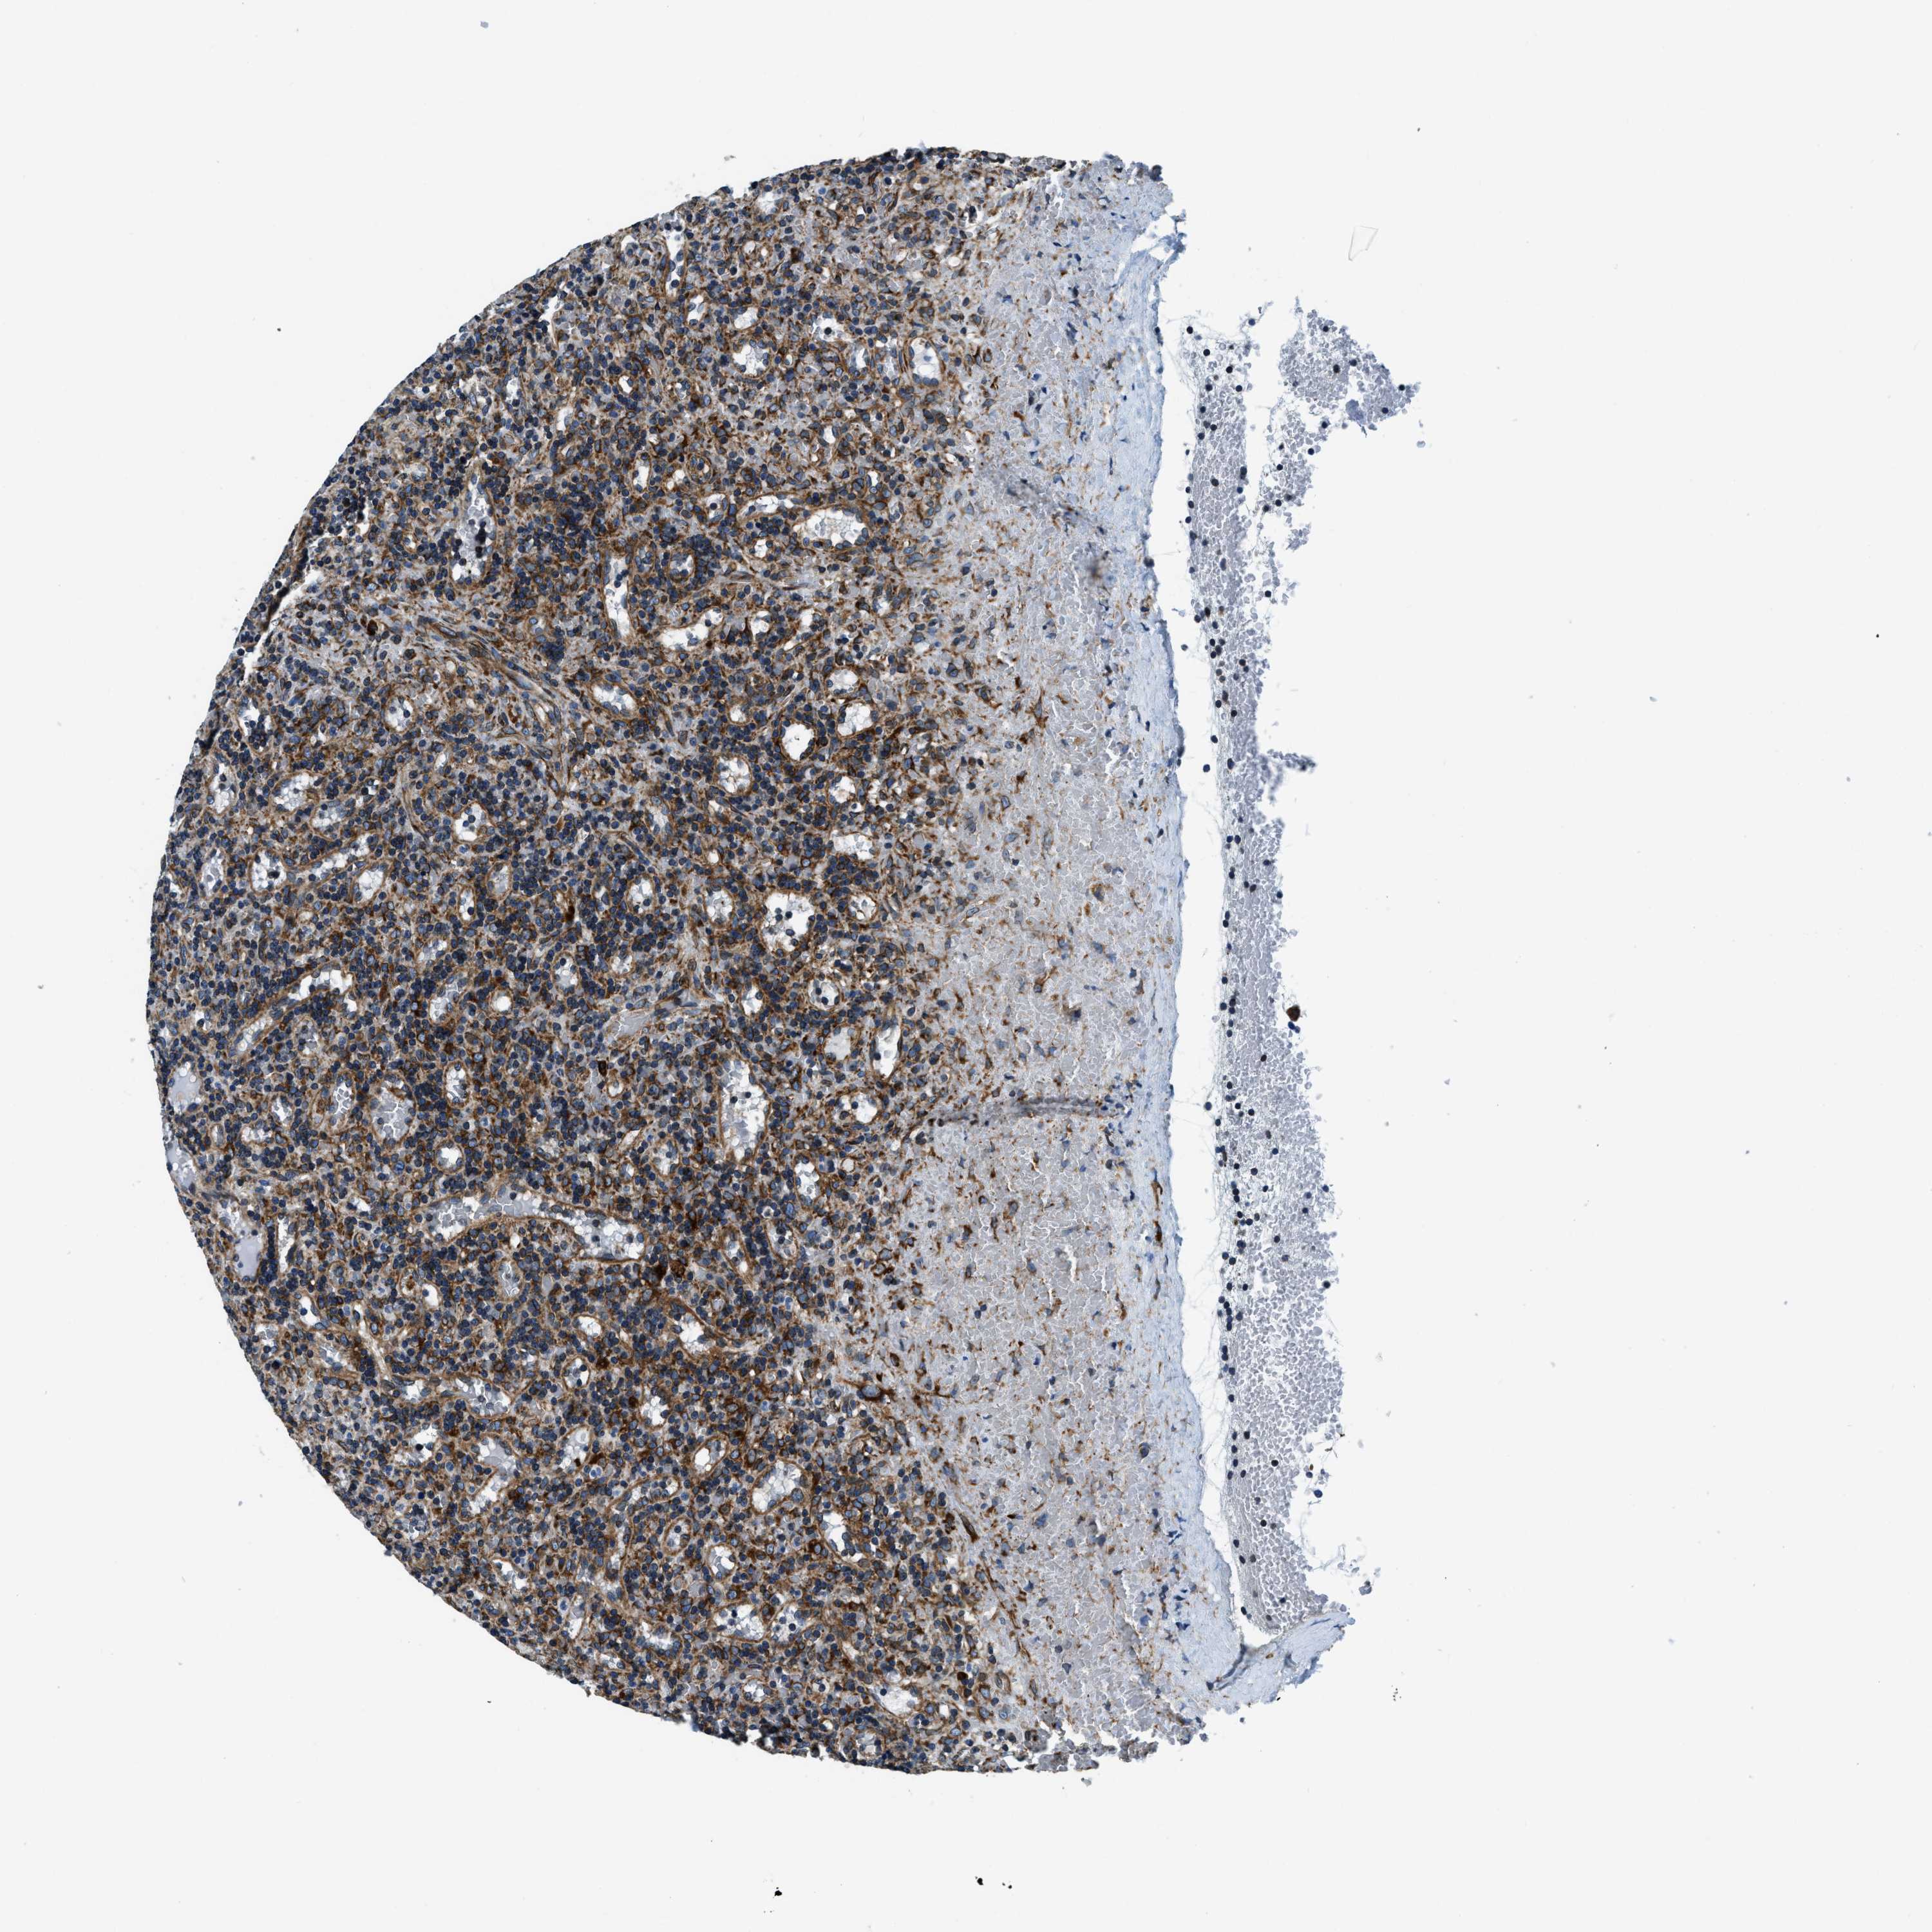

LYMPHOMA - Protein expressioni

A mouse-over function shows sample information and annotation data. Click on an image to view it in a full screen mode. Samples can be filtered based on level of antibody staining by selecting one or several of the following categories: high, medium, low and not detected. The assay and annotation is described here.

Each image is clickable and will lead to virtual microscopy that enables deeper exploration of all samples and also displays staining intensity scores, fraction scores and subcellular localization as well as patient and tissue information for each sample.

Antibody HPA019698

Staining

High

Intensity

Strong

Quantity

>75%

Location

Nuclear

Hodgkin's disease, NOS

Malignant lymphoma, non-Hodgkin's type, High grade

Malignant lymphoma, non-Hodgkin's type, Low grade